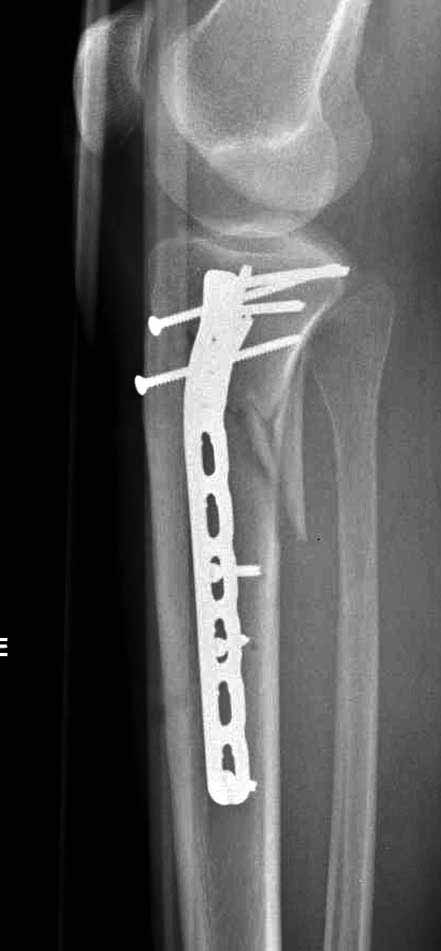

Если у вас, кроме пластины, нет другого альтернативного варианта, тогда, учитывая мягкотканые проблемы с наружной стороны, я бы рекомендовал операцию делать в два этапа. Преимущества, сперва репозиция и фиксация перелома с медиальной стороны, а затем, после улучшения состояния мягких тканей, зафиксировать с латеральной стороны. Современные пластины имеют латеральный Jig для перкутанных мини доступов.

В приложении этапы фиксации Both Column Fx и пластиной Synthes для плеча при переломе медиального мыщелка.